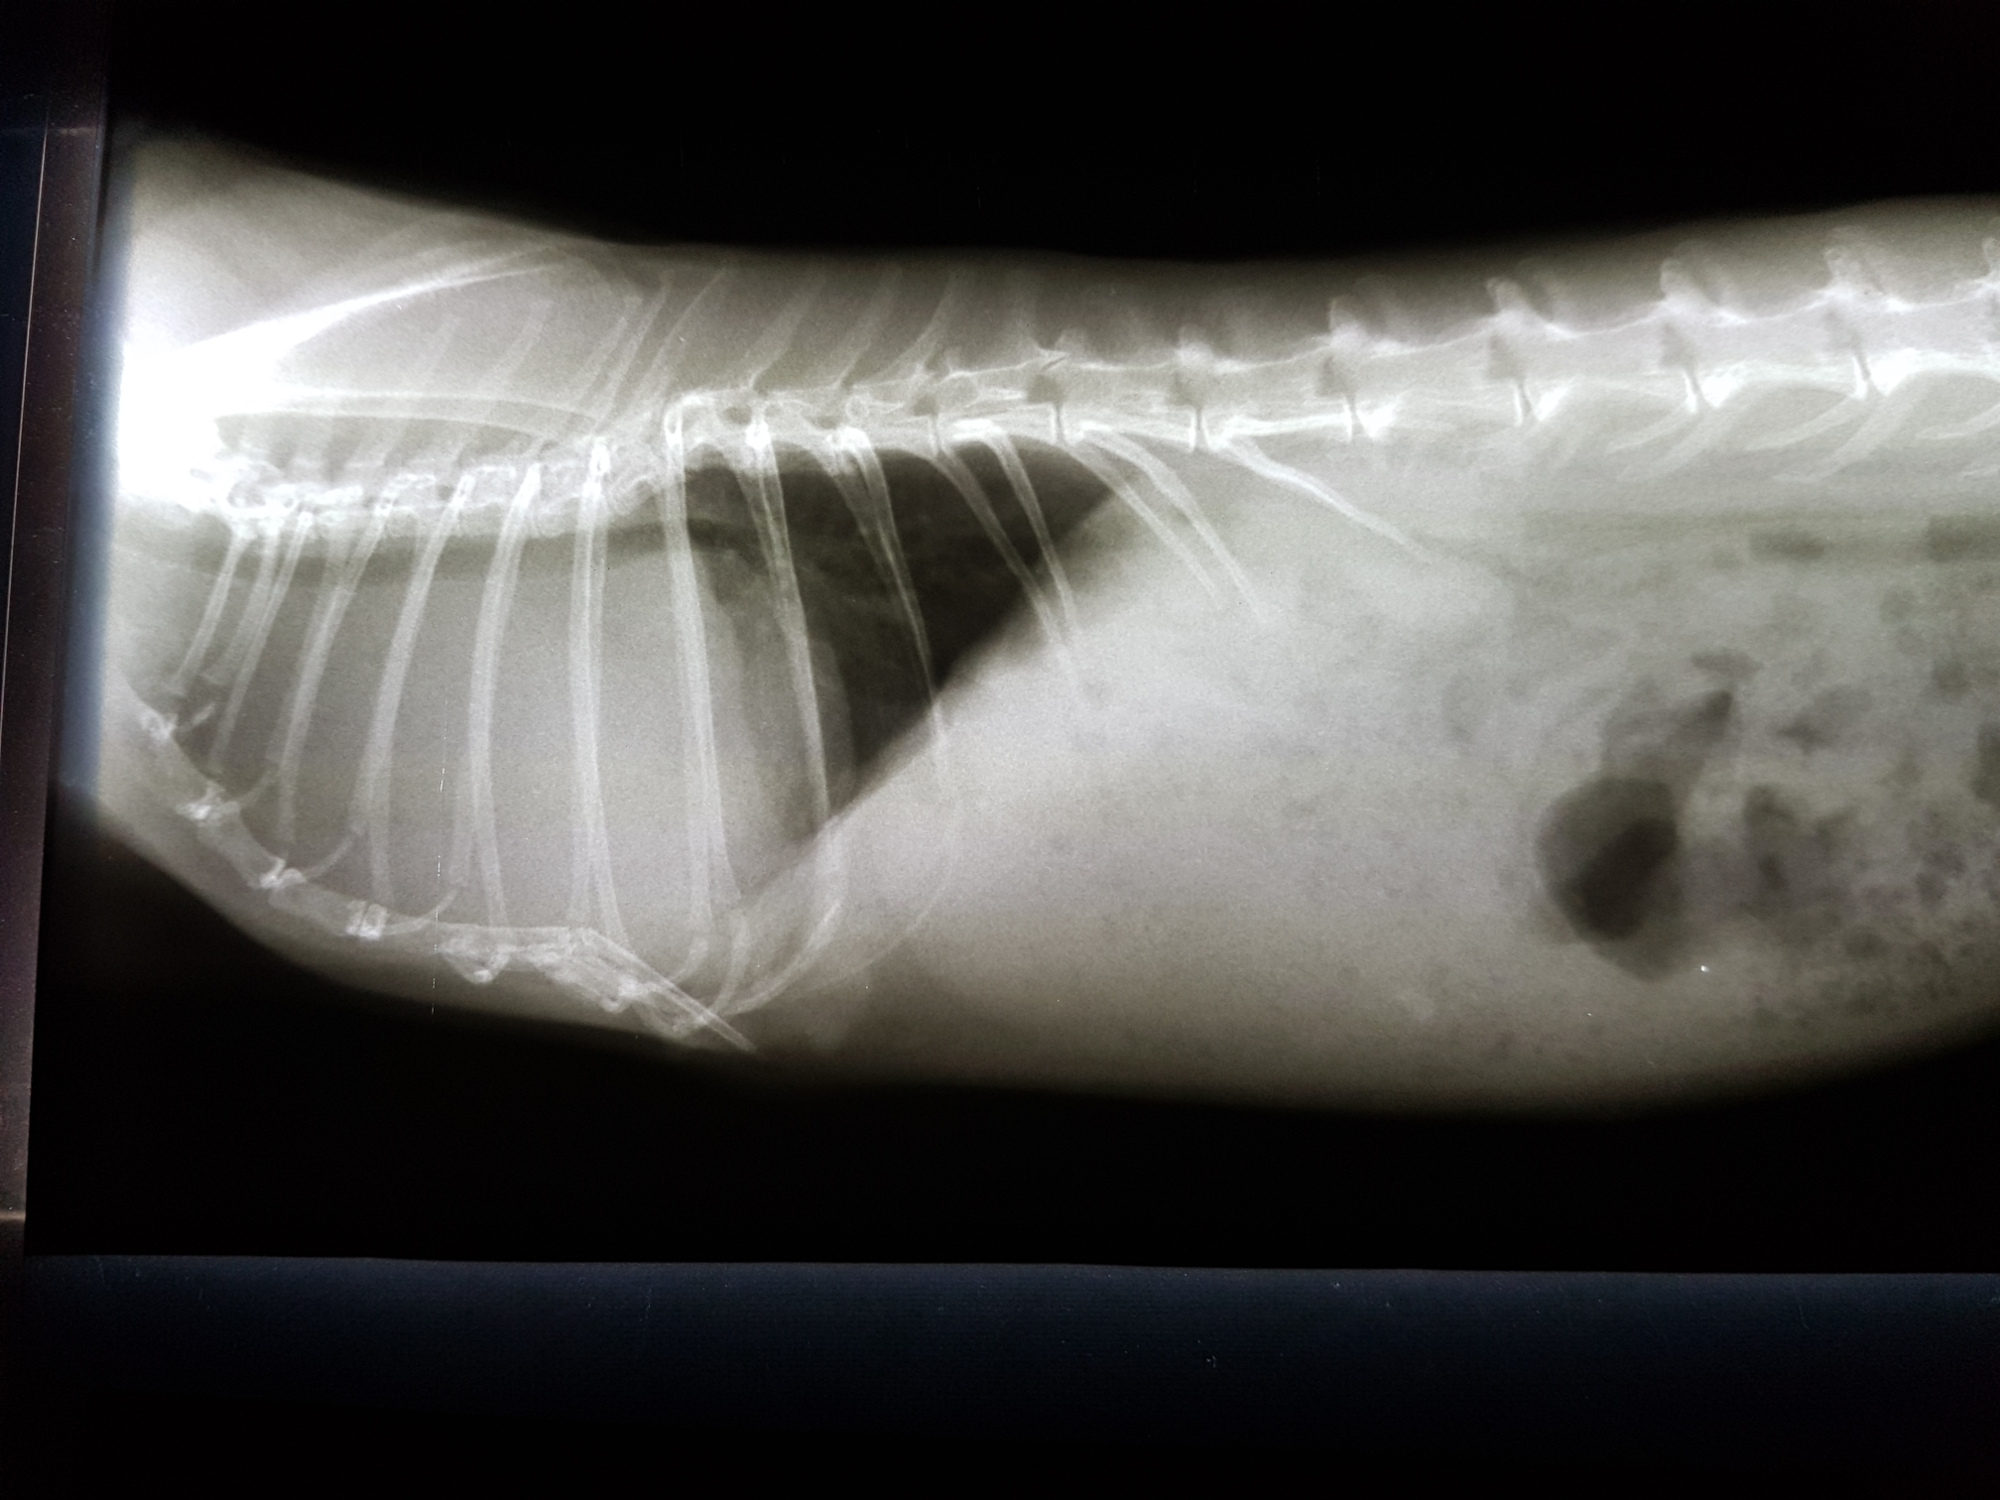

Ein Kaninchen mit Atembeschwerden oder den beschriebenen Augenveränderungen sollte zunächst geröngt werden. Hierdurch lassen sich Verschattungen im Brustkorb schnell und einfach erkennen und es muss anschließend nur noch ermittelt werden, ob es sich dabei um einen Tumor oder eine (reine) Herzerkrankung handelt. Letztere kann zu einem vergrößerten Herzen oder einem Erguss führen, was per Röntgendiagnostik nicht immer von einem Tumor zu unterscheiden ist.

Besteht eine entsprechende Verschattung, ist ein Herzultraschall angezeigt. Dabei können das Gewebe und die Herzfunktion eindeutig beurteilt werden. Dies ist auch deshalb von Bedeutung, da die Herzfunktion durch einen benachbarten Tumor beeinträchtigt werden kann. In diesem Fall muss das sekundäre Herzproblem in die Tumortherapie mit einbezogen werden.

Steht fest, dass es sich um einen Tumor handelt, ist als weitere Diagnostikmaßnahme das Entnehmen einer Gewebeprobe (Biopsie) möglich. Dies erfolgt in einer kurzen Narkose unter Ultraschallkontrolle. Auf die Weise kann bestimmt werden, um welche Tumorart es sich handelt, was je nach Therapie von Bedeutung sein kann.